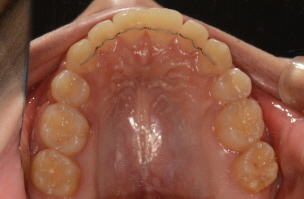

돌출입과 잘 다물어지지 않는 입이 고민이셨던 주**님! 한 눈에 보기에도 너무나 달라진 모습이죠?\r\n일년 반 남짓한 교정기간동안 바른이와 함께 해주셔서 감사합니다~^^*

교정 시작 교합면

교정 완료 교합면